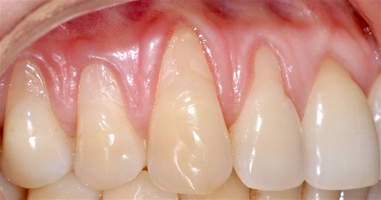

Во всех случаях применения аутотрансплантата и ТМО (dura mater) наблюдается сопоставимый положительный клинический результат по всем параметрам оценки рецессий десны (табл. 4). В случае нескольких зубов в области наиболее глубоких рецессий с наименьшими клиническими показателями имеет место сохранение класса рецессии не более первого класса (9 зубов) и глубиной не более 2 мм, 1.6 зуб — 3 мм.

В зарубежной литературе встречается также совокупный показатель эффективности лечения рецессий десны — процент закрытия корня зуба — отношение разница между конечным и исходным значениями глубины рецессии к исходному значению в процентах. Положительный результатом лечения является значение равное или более 80% [4]. Использование только показателя глубины рецессии десны для анализа эффективности лечения без учета остальных показателей (ТКД, ШКД, РРД, ЗДК) не дает полной картины результата и может быть применимо только в совокупности с другими показателями (рис. 6а-й).

Так в нашем случае процент закрытия корня зуба наблюдается больше 80% у 13 зубов. Менее 80% — у 11 зубов. Это связано с сохранением класса рецессии после лечения в области зубов с наибольшим классом рецессии и наибольшим показателем глубины рецессии. При этом средний показатель всех 24-х оперированных зубов — 83,1%. При этом среднее значение процента закрытия корня зуба для зубов с положительным результатом (более 80%) составляет 96,65%. Среднее значение для результатов менее 80% — 54,73, что связано с изменением глубины рецессий с 6 мм до 3 мм, с 4 мм до 2 мм и с 2 до 1 мм. При этом для аутотрансплантата и для ТМО результаты сопоставимы.

Послеоперационный период после всех операций протекал спокойно, без воспаления и особенностей, реактивный отек соответствовал норме в случае применения аутотрансплантата и ТМО (dura mater).

Реактивность в области применения ТМО и аутотрансплантата была сопоставима и сравнима с травмой мягких тканей при хирургическом вмешательстве. Имеет место реакция в обоих случаях на операцию, но на материал ТМО реакция отсутствует.